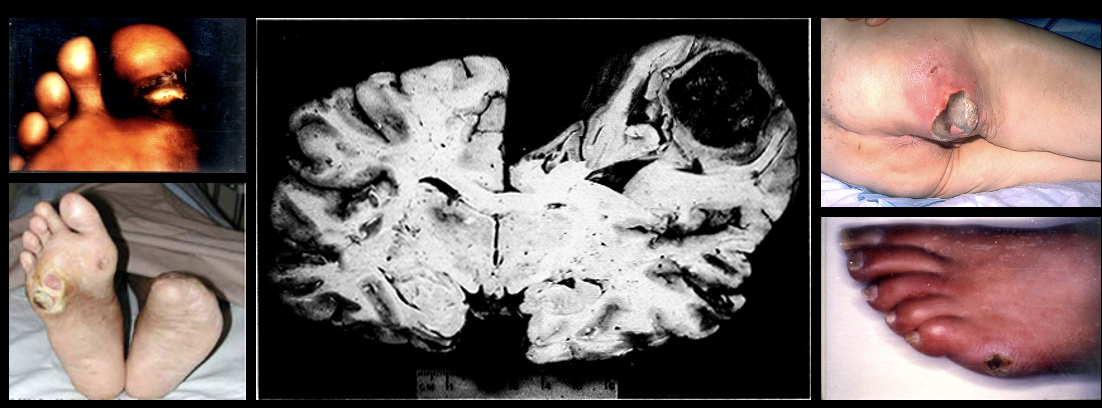

Coagulative necrosis

Necrosis causes by ischemia, in which cell membrane remains intact but organelles dissolve. Found in solid organs (heart, kidney, live)

Ex: early pressure sores

Caseous necrosis

"Cheesy” necrosis found in lungs, bone, and lymph nodes. Cells die, disintegrate and then clump together.

Ex: Miliary tuberculosis, mycobacterioum tuberculosis

Liqufactive necrosis

Necrosis with abscess formation of tissue by lysosomal enzymes due to infection. Found in brain tissue, skin, wound, joint infections

Ex: late pressure sores

Fatty necrosis

“Chalky” necrosis caused by acute pancreatitis and abdominal trauma, in which tissue is replaced by fat.

Fibrinoid necrosis

Necrosis caused by trauma in blood vessel walls, where the boy attacks blood vessels through autoimmune response.

Ex: organ transplant rejection